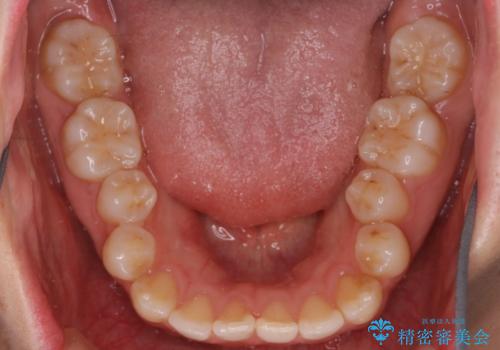

- 患者様は歯並びの乱れを気にされて来院されました。特に小臼歯の捻転(ねじれ)が強く、見た目だけでなく噛み合わせにも影響がありました。できるだけ目立たない方法を希望されていたため、インビザライン(マウスピース矯正)を基本としつつ、より精密な動きが必要な部分にはワイヤー矯正を併用する計画を立てました。また、小臼歯の捻転については**部分矯正(MTM:Minor Tooth Movement)**を取り入れ、効率的に改善を目指しました。

まず、全体の歯並びを整えるためにインビザラインを使用し、徐々に理想的な位置へと歯を移動させました。一方で、ねじれの強い小臼歯に対しては、**部分的なワイヤー矯正(MTM)**を行い、より精密なコントロールを実施。約2年の治療期間を経て、歯並びと噛み合わせが整い、見た目の美しさだけでなく、機能的な改善も達成しました。患者様からは「自然な仕上がりで、自信を持って笑えるようになった」と喜びの声をいただきました。